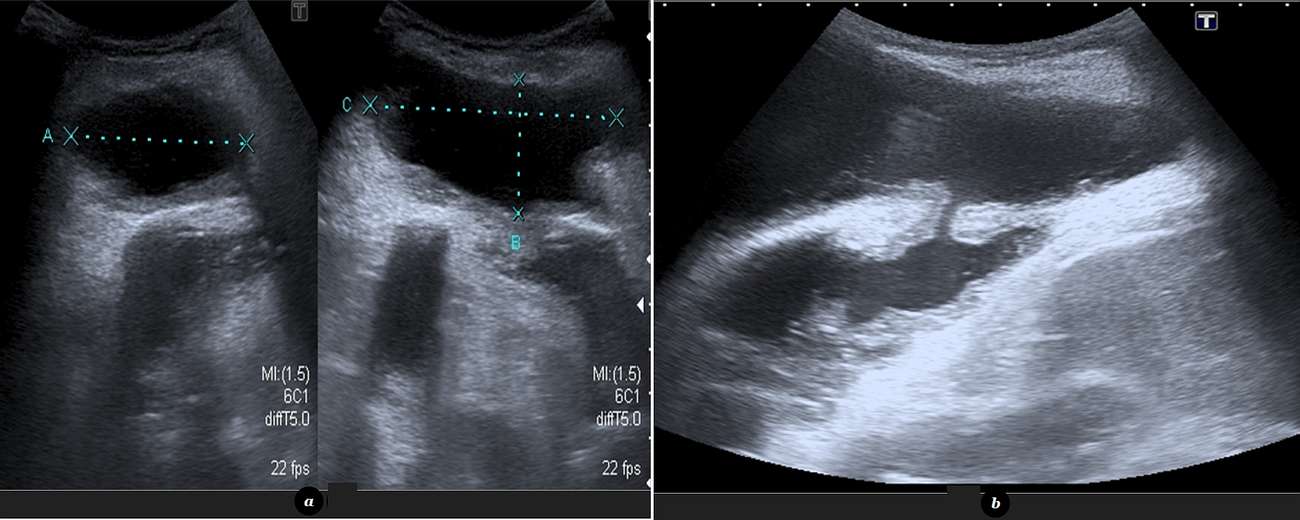

Chest radiography demonstrated a loculated left pleural effusion with associated soft-tissue opacity in the left chest wall. An abdominal ultrasound (US) was performed in order to better characterize the radiographic findings, showing a subcutaneous fluid collection with fine internal debris, measuring 5 x 3 x 7 cm, that communicated with the pleural cavity through a well-defined tract (image below).

While chest radiography can suggest the diagnosis, demonstrating a loculated pleural effusion in a patient with past history of pulmonary tuberculosis presenting with an anterior chest wall mass, the definitive imaging findings are usually seen with CT. Contrast-enhanced CT clearly demonstrates the existence of a communication between the empyema (i.e.: a loculated pleural effusion with thickened and enhancing pleural surfaces) and a well-deliniated chest wall fluid collection with thickened and enhancing walls, representing an abscess [6]. US and CT can also aid in the therapeutic process, guiding the thoracostomy necessary to drain the pleural cavity.